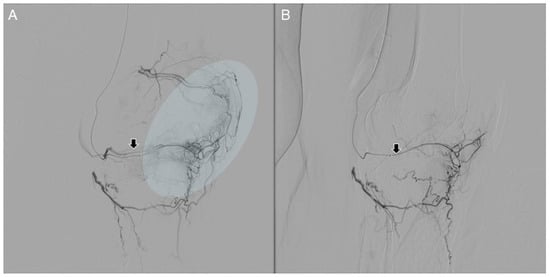

5. Embolization Procedure